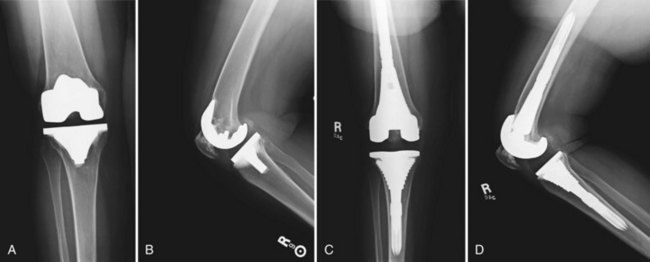

Mobile Bearing Total Knee Arthroplasty Musculoskeletal Key Mobile bearing (mb) total knee arthroplasty (tka) designs offer the theoretical advantage of increased implant conformity and contact area while minimizing stresses transmitted to the fixation interface. Subscribed 62 6.4k views 13 years ago comparison of mobile bearing total knee to partial knee replacement more. The mobile bearing (mb) concept in total knee arthroplasty (tka) was developed as an alternative to fixed bearing (fb) implants in order to reduce wear and improve range of motion (rom), especially focused on younger patients. The oxford partial knee is intended for use in individuals with osteoarthritis or avascular necrosis limited to the medial compartment of the knee and is intended to be implanted with bone cement. Partial knee performed by 13 different surgeons. surgical time was measured from insertion of the first bone pin to the acceptance of the final trial components. the average sur ical time for all surgeons was 56 ± 20 minutes. the shortest average surgical time for an individual surgeon was 38. Mobile bearing (mb) total knee arthroplasty (tka) designs have proposed biomechanical benefits, including improved patellar tracking and reduction in polyethylene wear.